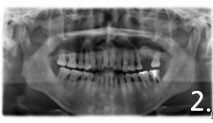

Before the surgery. There is not enough bone at back site to place implants

Implant placement and sinus bone graft were performed simultaneously on right side. Only sinus bone graft was performed on left side due to the lack of the residual bone to place implant simultaneously

Implant placement was performed a few months after sinus bone graft

All implant crowns were fabricated and delivered. All teeth functions were restored.